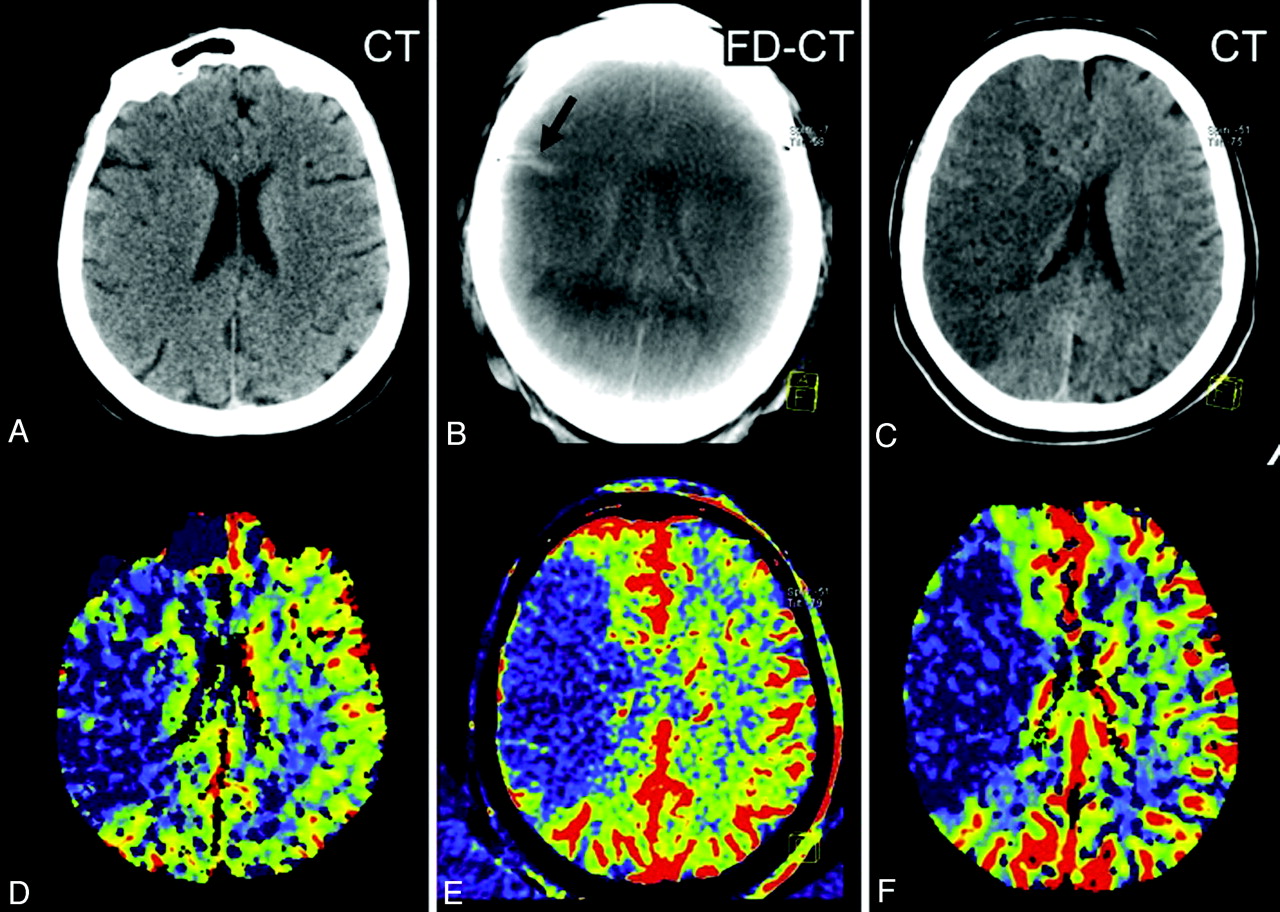

Patient 9. The initial CT (A) and PCT CBV map (D) showed no abnormality. After successful revascularization, there was a small lesion (oligemia) identified on the FPCT CBV map (E, black arrows). This corresponded well with the lesion identified on the follow-up PCT CBV map (F, black arrows). The CBV abnormality observed on the FPCT CBV map (E) matches the sizes of the infarct observed on the follow-up MSCT (C, black arrows). Brain parenchyma reconstruction of the FPCT (B) was without findings.

Patient 2. A CBV lesion (oligemia) is observed on the initial PCT CBV map (D, red arrows); the CT scan (A) was without findings. Revascularization was not successful, and the abnormality had increased in size on the FPCT CBV map perform at the end of treatment (E). No evidence of hemorrhage or contrast extravasation was seen on the corresponding FPCT (B). On the 24-hour follow-up, the infarct observed on the MSCT (C, red arrows) corresponds to the CBV abnormality identified on both the FPCT CBV map (E) and the follow-up PCT CBV map (F).

Patient 11. The initial PCT CBV map (D) shows a large area of CBV abnormality (oligemia). No clearly defined infarct was identified on the initial CT (A). Revascularization was not successful. On the FPCT CBV map generated immediately after treatment, the CBV abnormality (E) was unchanged from that observed on the inital PCT study. A small area of hyperattenuation was seen on the FPCT performed immediately after treatment (B, black arrow). This was felt to be due to contrast medium extravasation. The follow-up PCT CBV map showed an abnormality corresponding to those observed the initial study and in the study performed immediately after treatment (F). The follow-up CT showed no evidence of the previously observed area of hyperattenuation. The area of infarction seen on the follow-up MSCT (C) matches that seen on the 3 CBV studies.